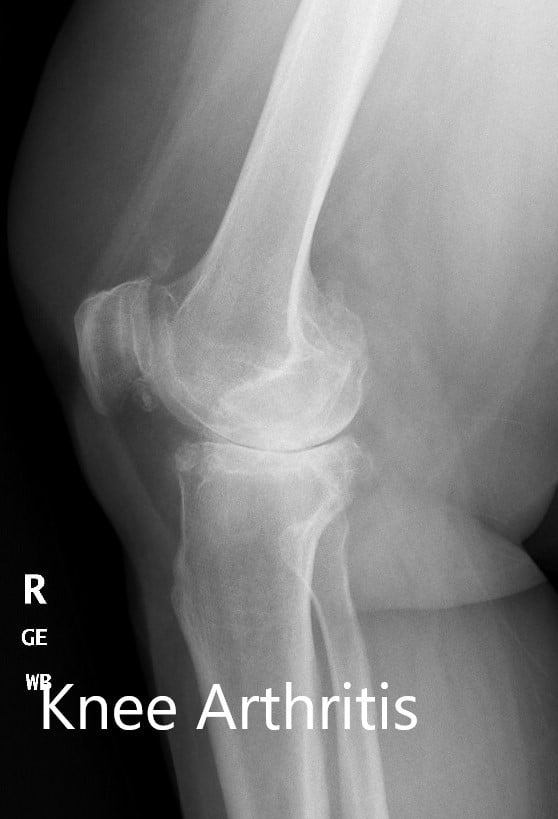

Imaging studies revealed severe tricompartmental osteoarthritis of the right knee. Considering the patient’s lifestyle limiting knee pain, he was advised customized total knee replacement. Risks, benefits, and alternatives were discussed with the patient. He agreed to go ahead with the surgery.

Preoperative X-ray of the right knee showing AP and lateral views.